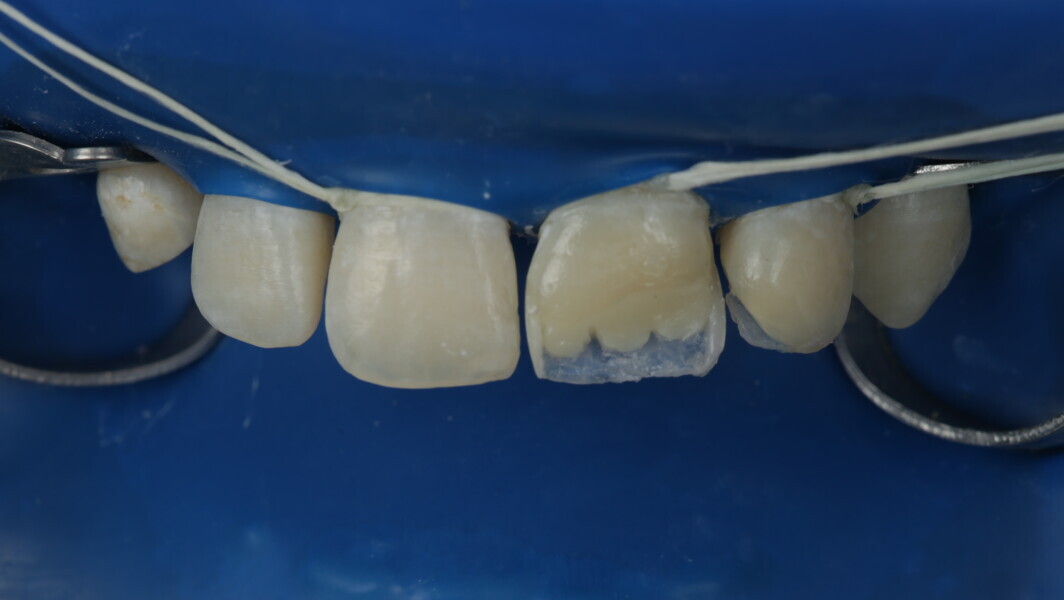

Fig 25-30: Layering protocol step by step

Fig 31-41: Polishing protocol and post-op